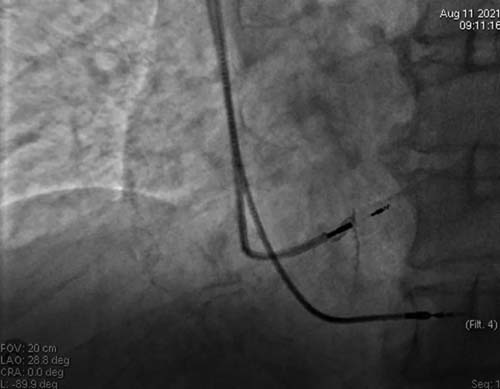

术中通过精细操作,将电极精准定位于左束支(图2),经过测试,起搏器可在在0.6v电压下实现完美的选择性左束支起搏,QRS宽度仅为98ms, 术后心电图基本恢复正常(图3)。

图2 左束支电极定位